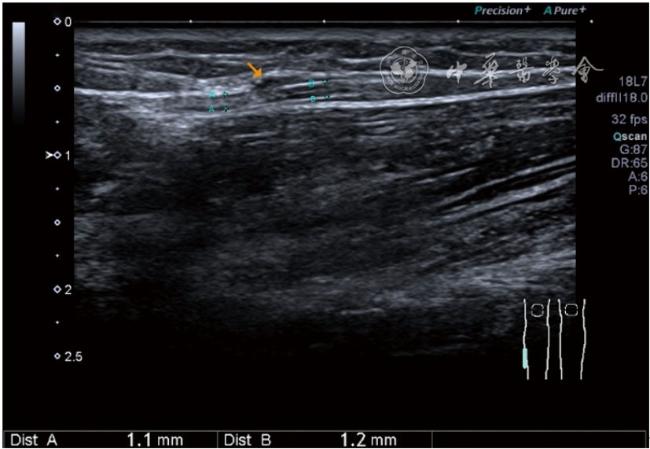

4.腓总神经分支卡压的治疗。常见腓浅神经、腓深神经感觉支卡压。主要表现为足背侧的感觉减退。腓深神经只支配第一、二足趾之间的感觉,腓浅神经支配的感觉区域较多,第一、二足趾之间外的足背感觉均由腓浅神经支配,根据感觉障碍区域确定卡压神经,超声可以明确卡压部位和原因。超声可显示卡压神经增粗,回声减低,局部软组织回声不均匀等(图4445)。治疗以液压松解药物注射为主。以腓深神经为例进行介绍。常见卡压部位在小腿和足背部。根据卡压部位不同,患者采取不同的体位。如果在小腿部采用平卧位,膝关节伸直位即可。穿刺区域常规消毒,探头涂抹耦合剂后套入无菌手套碘伏消毒或使用无菌耦合剂。将探头置于患者皮肤表面,小腿部位采用短轴扫查,确定神经卡压最明显的部位后,用一次性5 ml注射器,应用25G注射针头抽吸0.5%利多卡因4 ml+地塞米松3 mg平面内进针到达神经周围,注意回抽无血液回流后进行注射(图46),完成注射松解,拔出针头,局部压迫3分钟,创可贴覆盖。如果在足背部可以采取平卧位,屈髋、屈膝将足平放于治疗床面。治疗前准备同小腿部,采用长轴显示神经,确定神经卡压最明显的部位后,用一次性5 ml注射器,应用25G注射针头抽吸0.5%利多卡因2 ml+地塞米松1 mg平面内进针到达神经表面进行注射(图47),完成注射松解,拔出针头,局部压迫3分钟,创可贴覆盖。

图46 腓深神经在小腿近端腓深神经、腓浅神经分开处卡压及穿刺注射治疗超声图像

图47 腓深神经足背处卡压及穿刺注射治疗超声图像